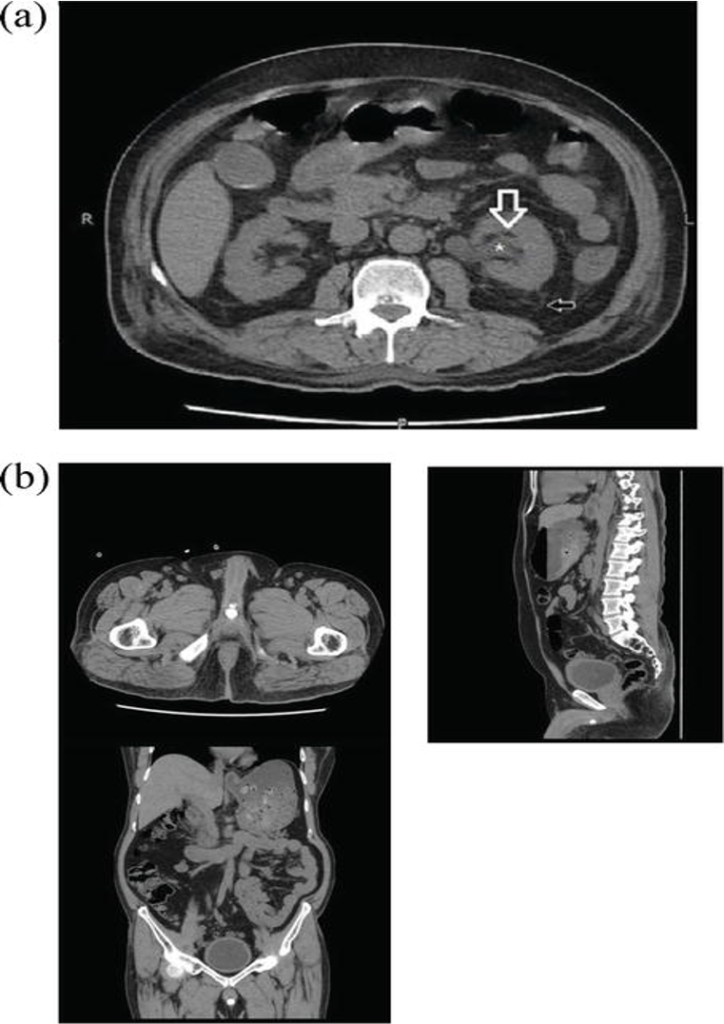

View of perirenal fat stranding in non-contrast computed tomography.

(a) Hydronephrosis (*), reduced peripelvic fat (white arrow) and increased perinephric fat stranding (black arrow) as compared to contralateral side.

(b) CT KUB axial, sagittal and coronal sections demonstrating multiple calcific densities near the bulbar urethra likely representing urethral diverticulum with stone formation.

CT KUB axial, coronal and sagittal sections demonstrating a calculus in the prostatic urethra.

CT KUB axial supine and prone positions demonstrating a left-sided VUJ calculus.